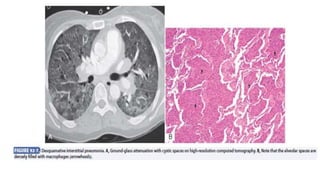

• Desquamative Interstitial Pneumonia

Desquamative interstitial pneumonia is a rare entity (<3% of all ILDs)

that may represent a form of respiratory bronchiolitis–associated ILD

extending into the alveolar spaces and alveolar walls. Although most

affected individuals are cigarette smokers, the histologic pattern of

desquamative interstitial pneumonia may also occur in

pneumoconiosis, rheumatologic disease, and drugassociated ILD.

Patients are often initially seen with advanced disease and striking

hypoxemia. The histopathology features of desquamative interstitial

pneumonia are characterized by accumulation of pigmented alveolar

macrophages within the alveoli. Histologic changes within the

respiratory bronchioles and within the alveolar spaces can coexist and

represent a histopathologic spectrum of alveolar macrophage

accumulation.

Diagnosis

• Pulmonary function tests reveal a restrictive lung defect and

decreased Dlco with or without coexisting airway obstruction.

• The chest radiograph shows patchy basal consolidation with a lower

lobe and peripheral predominance

• HRCT shows bilateral symmetrical ground-glass opacities with a

predominantly basal and peripheral distribution as well as diffuse

alveolar septal thickening.

• Irregular linear opacities, typically associated with traction

bronchiectasis, may be noted.

• Fluid recovered from BAL quite often shows increased numbers of

pigmented alveolar macrophages, frequently with increased

neutrophils. Histopathologic findings on biopsy include diffuse

alveolar septal thickening, hyperplasia of type II pneumocytes, and

intense accumulation of intra-alveolar granular pigmented

macrophages in a uniform manner fibrosis is minimal.